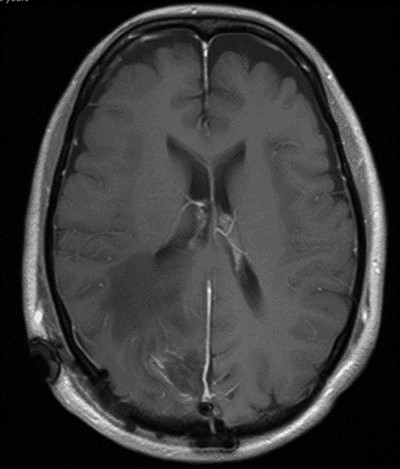

A 52-year-old female presented with headache and visual disturbance. She had no significant past medical history. On examination, a left homonomous inferior quadrantopia was noted. CT and then MRI imaging revealed a solitary 3-cm right parieto-occipital extra-axial lesion with associated dural tail and surrounding oedema (Fig. 1). Her headaches improved with a short course of steroids and the neuro-oncology MDT recommendation was for surgical excision of the suspected meningioma.

Axial view of a T1 weighted MRI post-gadolinium enhancement demonstrating the appearance of a 3-cm right parieto-occipital extra-axial mass with bony involvement and adjacent small nodule. Most in keeping with a meningioma.